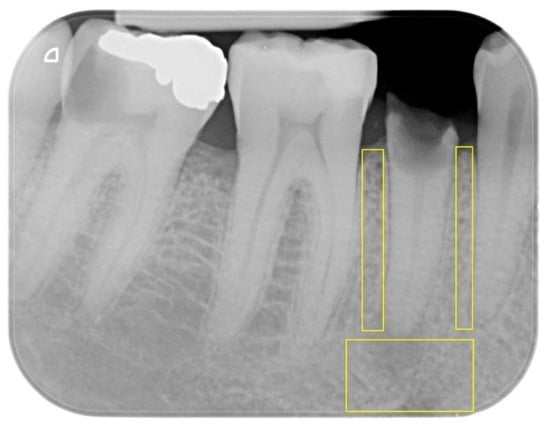

The present study explores bone healing patterns induced by orthodontic (OE) and surgical extrusion (SE) of structurally compromised teeth, where extrusion techniques are commonly used in rehabilitation. Changes in the trabecular bone were assessed by means of fractal analysis (FA) of consecutive periapical [...] Read more.

The present study explores bone healing patterns induced by orthodontic (OE) and surgical extrusion (SE) of structurally compromised teeth, where extrusion techniques are commonly used in rehabilitation. Changes in the trabecular bone were assessed by means of fractal analysis (FA) of consecutive periapical radiographs. (2) The present study is a retrospective case–control study. Pre- and post-treatment periapical radiographs from 44 adults undergoing orthodontic (OE) or surgical extrusion (SE) were retrieved. The radiographs were taken at T0 (pre-treatment), T1 (post-treatment), T2 (3-month follow-up), and T3 (6-month follow-up). Bone density (fractal dimension, FD) was analyzed in the apical and proximal bone regions (ROIs) of the extruded teeth, and both intra-group and inter-group differences were examined. (3) In all the regions of interest (ROIs), statistically significant intra-group differences in terms of bone density (FD) for both groups were found. In the OE group, the FD value increased, respectively, at T1, T2, and T3 in the apical ROI, compared to T0. For the proximal ROI, nearly the same trend was observed, respectively, at T1, T2, and T3 versus T0. As for the SE group, a statistically significant increase in the apical ROI was noted at T1, T2, and T3 when compared to T0. The same trend was registered in the proximal ROI compared to T0. However, no statistically significant inter-group differences in FD were detected between the two groups. (4) Orthodontic extrusion and surgical extrusion both resulted in an increased bone density (FD) despite the different healing patterns. Further prospective studies with a longer follow-up in this field are required. Full article

Figure 1